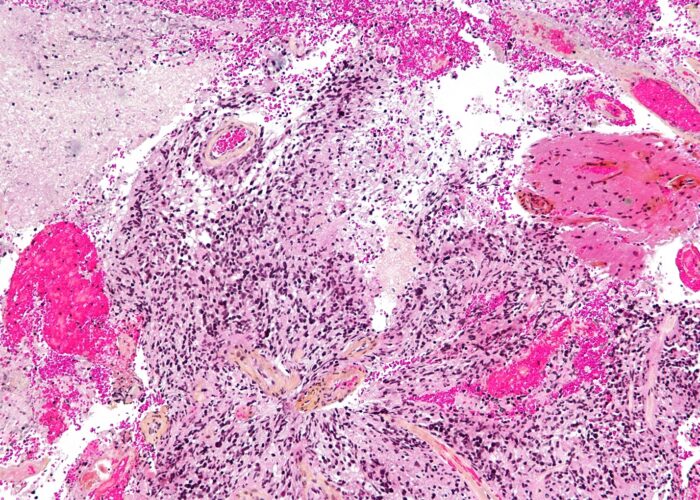

COMPOSITION FOR USE IN THE TREATMENT OF GLIOMA AND GLIOMA-INDUCED EPILEPSY

THERAPEUTIC TREATMENT AGAINST NEURODEGENERATIVE PRION DISEASES